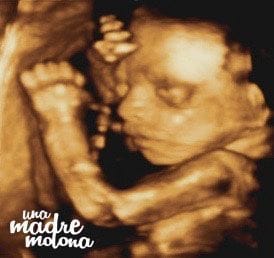

Y sin más dilación, os presento a ¡¡¡Minimolona!!!

¿No os parece increíble lo bien que se ve? marido y yo (bueno, y el resto de la familia molona) babeamos sin parar 😀 La chiquitina se pasó media sesión jugando con el cordón umbilical, lo cogía, se lo metía en la boca, lo volvía a soltar… ¡se mueve muchísimo!